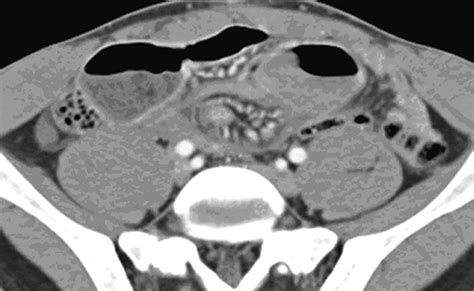

CT Scan Structural imaging of the abdomen Moderate (good for complications like obstruction)

The interpretation of a Meckel’s Diverticulum Scan requires expertise in nuclear medicine. A positive result is indicated by a “hot spot”—an area of increased radioactivity that appears in the lower abdomen during the imaging sequence. This “hot spot” corresponds to the area where the technetium-99m has accumulated in the gastric mucosa.

It is worth noting that a negative scan does not absolutely rule out the presence of a Meckel’s diverticulum. If the diverticulum lacks gastric mucosa or if the blood supply is compromised, the tracer may not accumulate sufficiently to be detected. In such instances, clinicians may consider repeat testing or moving toward surgical options if clinical symptoms are severe and persistent.